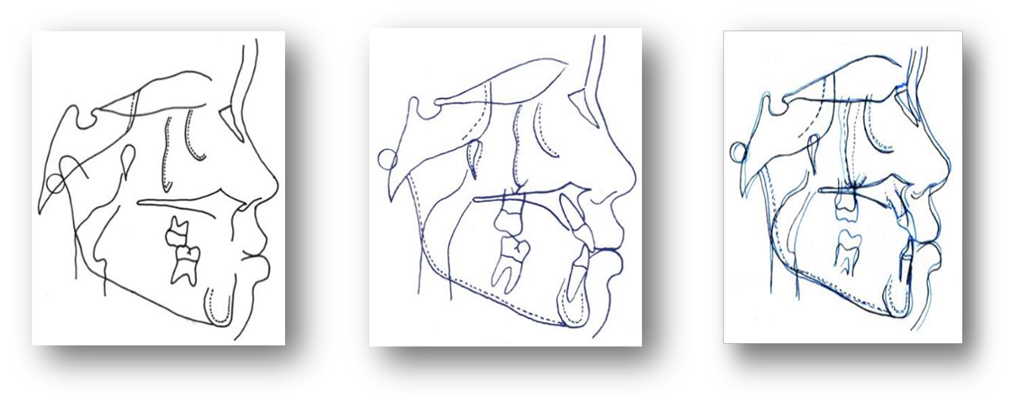

Figura 13. Análisis cefalométrico en las tres fases del tratamiento.

Figura 14. Análisis cefalométrico en las tres fases del tratamiento.